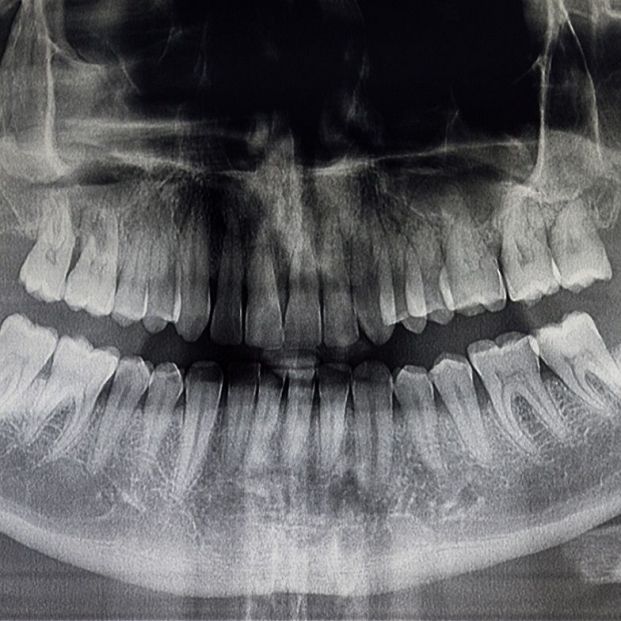

Los trastornos de la articulación temporomandibular (ATM) son un conjunto de patologías musculares y/o articulares que, con origen traumático, autoinmune, infeccioso o degenerativo, pueden ocasionar alguno de los tres signos principales: dolor, limitación de la movilidad mandibular y/o ruidos articulares.

La patología articular va casi siempre asociada a una dolencia y una sobrecarga musculares, en especial de los músculos masticatorios (masetero, temporal y pterigoideos), encargados de la movilidad y la posición de la mandíbula.